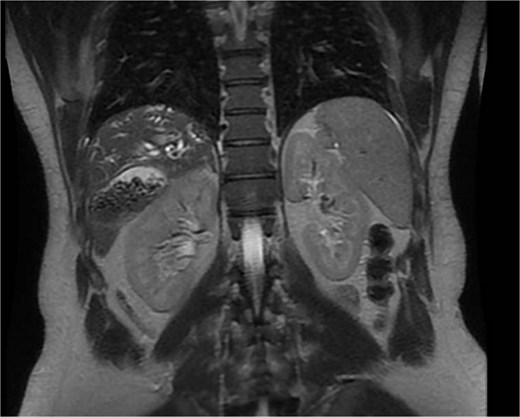

A 35-year-old male, medically free, presented to the emergency department with a 3-day history of epigastric abdominal pain. The pain was gradual in onset, colicky, non-radiating, and aggravated by fatty meals. It was partially relieved by analgesia. He reported nausea with two episodes of vomiting and dark urine, but denied fever, rigors, or bowel habit changes. His past surgical history included laparoscopic sleeve gastrectomy performed 7 years earlier, with subsequent weight loss of 40 kg, and anal fistulotomy 1 year prior. On examination, the patient was alert, oriented, and afebrile. Conjunctival icterus was noted. Abdominal examination revealed right upper quadrant and epigastric tenderness with a positive Murphy’s sign. Laboratory investigations showed: hemoglobin 14.8 g/dl, WBC 5 × 109/l, Alanine Aminotransferase (ALT) 341 U/l, Aspartate Aminotransferase (AST) 96 U/l, Alkaline Phosphatase (ALP) 250 U/l, Gamma-Glutamyl Transferase (GGT) 21 U/l, total bilirubin 121.9 μmol/l, and direct bilirubin 86.7 μmol/l. Ultrasound was done revealed multiple gallstones with gallbladder wall thickening, a dilated common bile duct (8 mm). Magnetic resonance cholangiopancreatography (MRCP) done and demonstrated an abnormally located subhepatic gallbladder, innumerable gallstones and sludge in a distended gallbladder with an 8 mm stone impacted at the gallbladder neck, moderate CBD dilation (1.1 cm), and a 6 × 4 mm distal CBD stone. (Fig. 1) Intrahepatic biliary radicles were dilated with a mildly irregular contour concerning for cholangitis. (Fig. 2).

MRCP, coronal views, demonstrating an abnormally located subhepatic gallbladder positioned inferior to the liver margin.